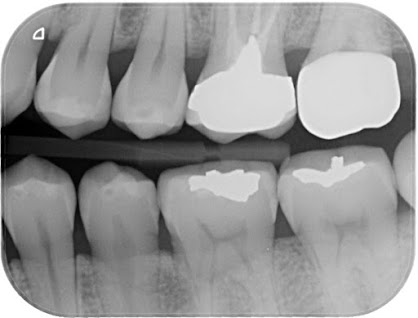

全瓷嵌體

贋復補綴